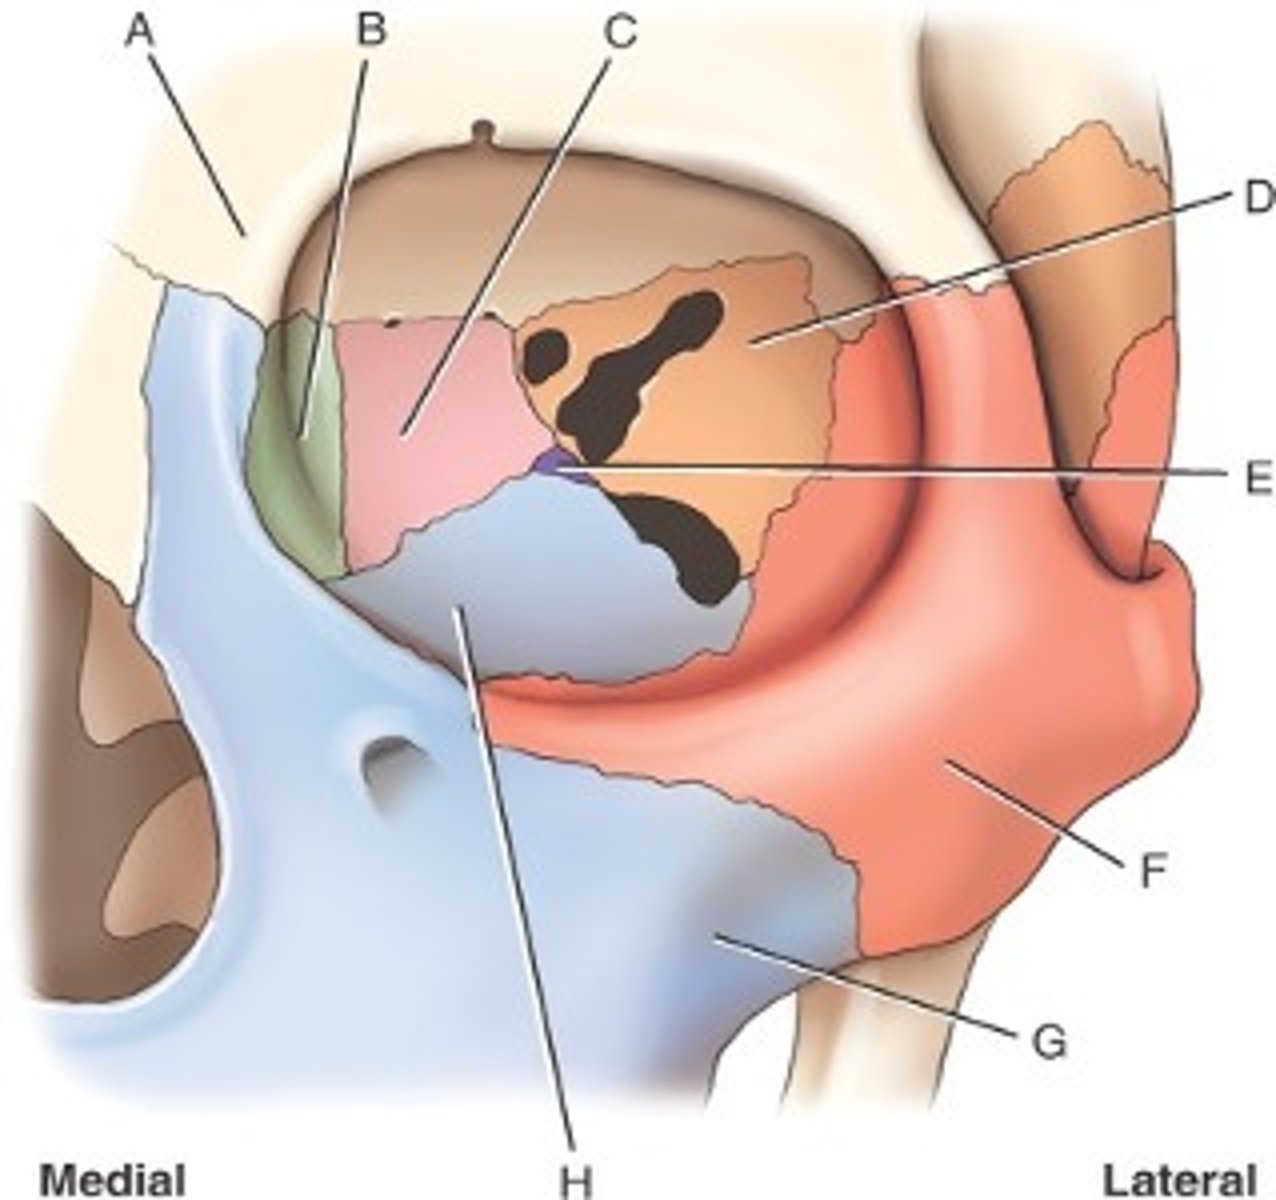

What is B

frontal bone

What is A

ethmoid

What is C

sphenoid

what is D

Palatine

What is E

Zygoma

What is F

Maxilla

What is G and H

optic foramen in orbit

sphenoid strut